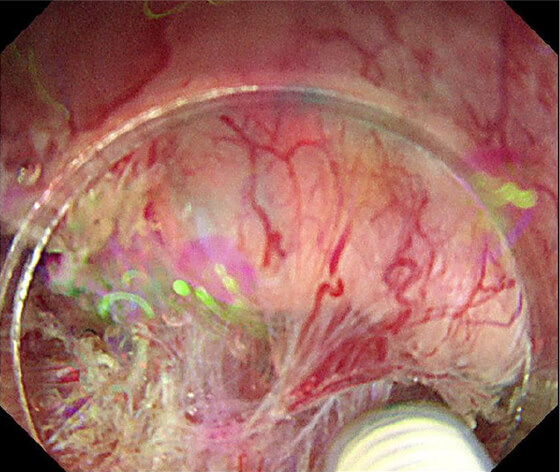

放射線療法後の遺残再発食道癌に対する光線力学的療法(PDT)も行っており、PDTの実施可能施設は九州で4施設のみ、長崎県内では当院が唯一の実施施設となっています。

PDT 5ヶ月後